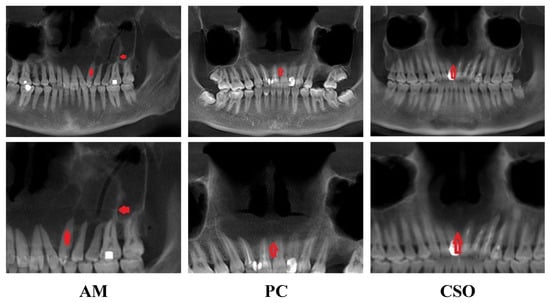

3.1. Sample Characteristics